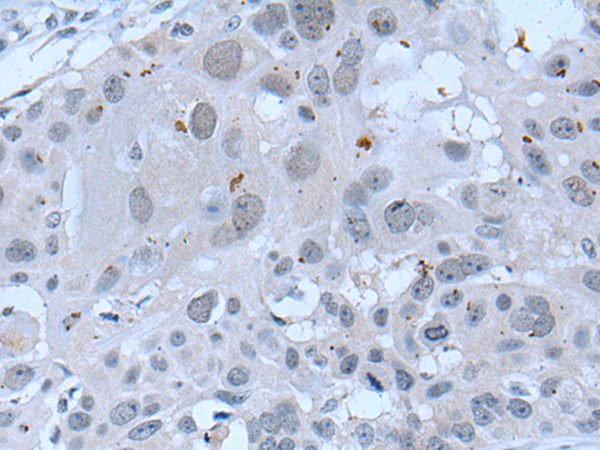

分类: 科研抗体货号: P12820别名: CENF; hcp-1; CILD31; PRO1779应用: IHC反应种属: Human

分类: 科研抗体货号: P12837别名: ZAP; ZC3H2; ARTD13; PARP13; FLB6421; ZC3HDC2应用: IHC反应种属: Human

分类: 科研抗体货号: P12836别名: C19orf7应用: IHC反应种属: Human, Mouse

分类: 科研抗体货号: P12818别名: ATG1; ATG1A; UNC51; hATG1; Unc51.1应用: IHC反应种属: Human

分类: 科研抗体货号: P12835别名: ZNF923应用: IHC反应种属: Human

分类: 科研抗体货号: P12816别名: Hxt; eHand; Thing1; bHLHa27应用: WB,IHC反应种属: Human, Mouse, Rat

分类: 科研抗体货号: P12834别名: ZNF903; KAISO-L1应用: IHC反应种属: Human, Rat

分类: 科研抗体货号: P12844别名: TIP20应用: IHC反应种属: Human, Mouse